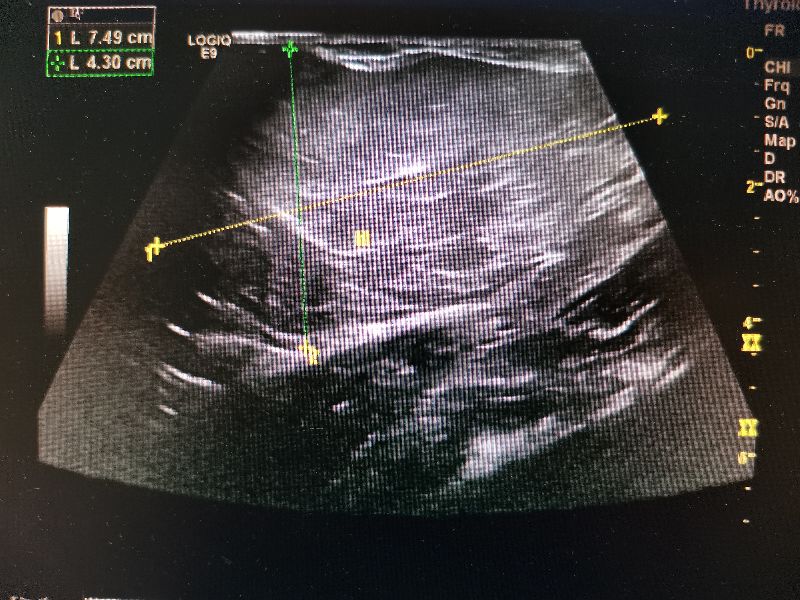

影像下看-我长这样!

手在皮外量,瘤在皮内泣